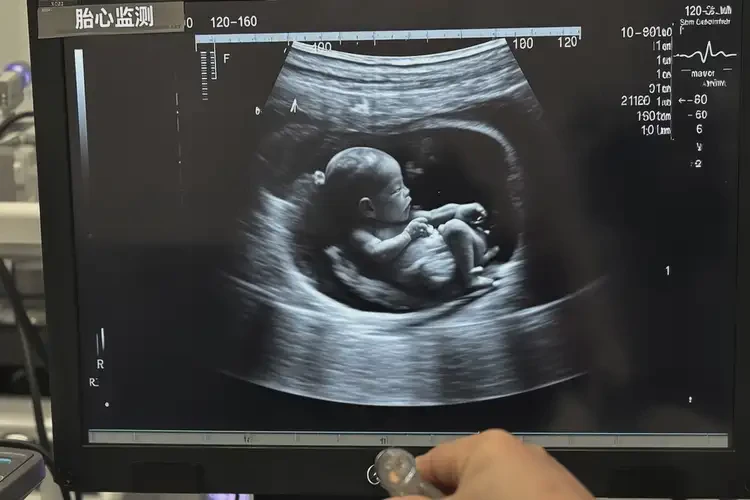

孕14周胎心170左右还能保住吗(图1)

• 超声检查:超声检查可以帮助医生了解胎儿的发育情况和是否存在其他异常。

孕14周胎心170左右还能保住吗(图2)